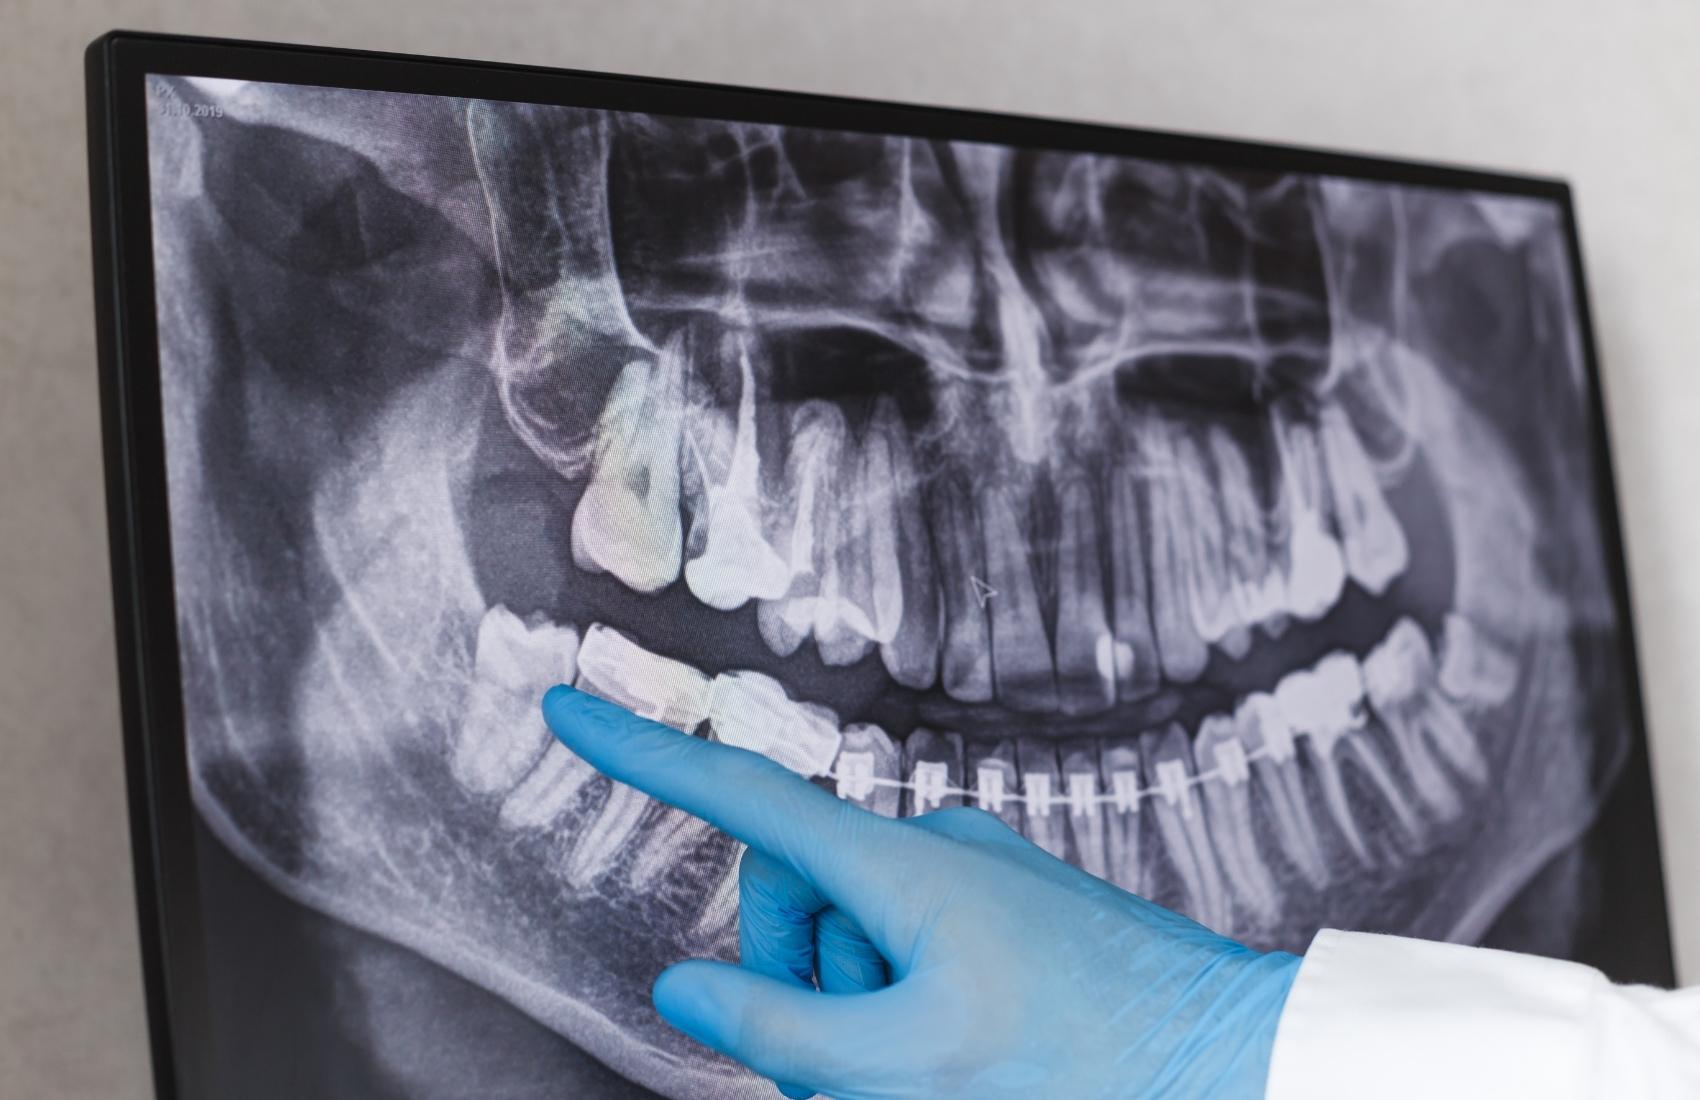

Panoramic X-rays show the entire mouth area all the teeth in both the upper and lower jaws on a single X-ray. This X-ray detects the position of fully emerged as well as emerging teeth, can see impacted teeth and helps diagnosis tumours.